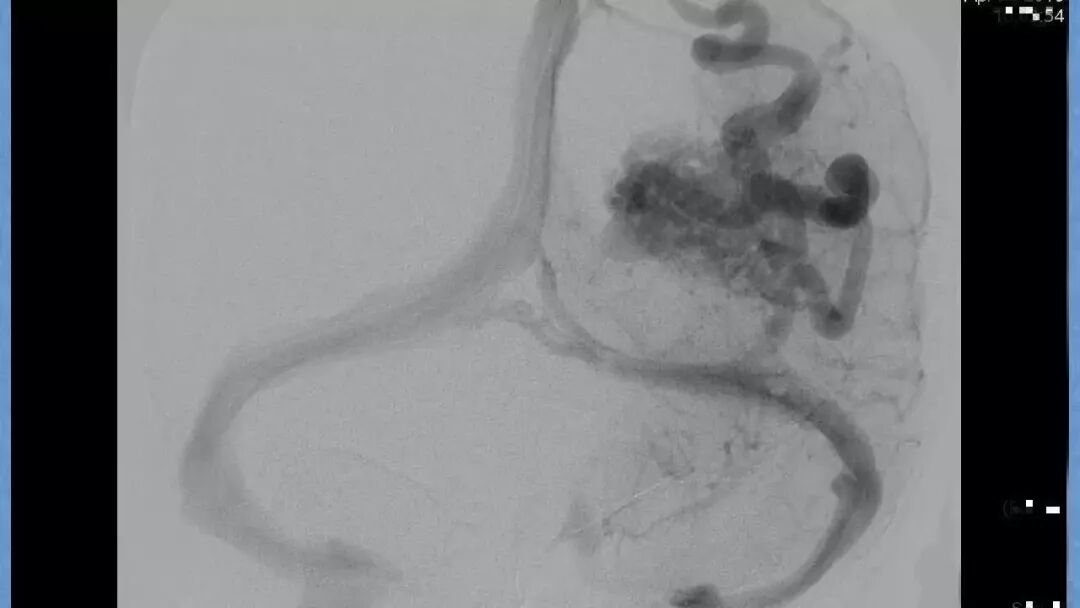

今天为大家分享的是《贝朗时间》第二十九期,湖北十堰市太和医院神经外科张力教授团队带来的:一个AVM患者的48小时纪实,欢迎阅读、分享!

张力教授:AVM切除术